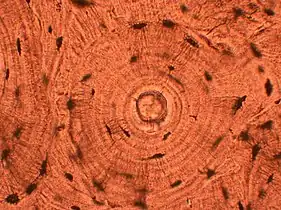

Water is removed from the sample in successive stages by the use of increasing concentrations of alcohol.[1] Xylene is used in the last dehydration phase instead of alcohol - this is because the wax used in the next stage is soluble in xylene where it is not in alcohol allowing wax to permeate (infiltrate) the specimen.[1] This process is generally automated and done overnight. The wax infiltrated specimen is then transferred to an individual specimen embedding (usually metal) container. Finally, molten wax is introduced around the specimen in the container and cooled to solidification so as to embed it in the wax block.[1] This process is needed to provide a properly oriented sample sturdy enough for obtaining a thin microtome section(s) for the slide.